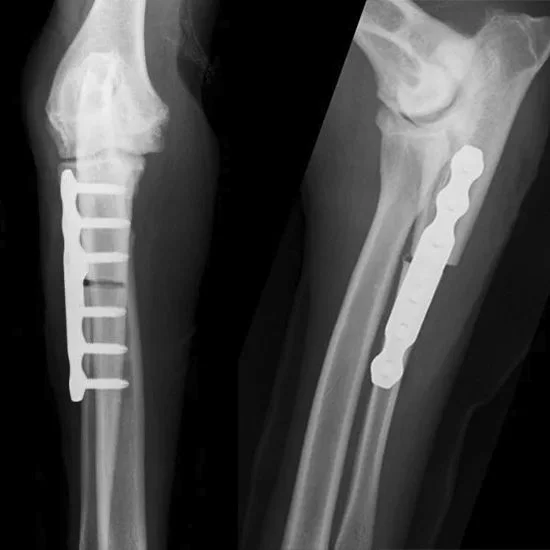

KYON ALPS® PAUL – Proximal Abducting Ulnar Osteotomy

The ALPS® PAUL-I and ALPS® PAUL-II plates impose a corrective limb alignment aimed at unloading the medial compartment of companion animals with medial compartment disease of the elbow.

ALPS® PAUL-I is the first generation PAUL plate based on ALPS® Technology.

The first generation ALPS® PAUL-I plate was invented and developed by KYON in collaboration with Dr. Ingo Pfeil in 2007.

ALPS® PAUL-II is a second generation PAUL plate. It is part of the ALPS® Product Range and thus combines the biological benefits of ALPS® Technology and the economical benefits of KYON Locking Screws KLS™.

• The implants offer strength and construct stability while minimizing damage of the vascular supply through ALPS® Technology.

• Clinically proven. More than 5,000 patients have been treated with ALPS® PAUL-I & ALPS® PAUL-II.

Procedure

A specially designed ALPS PAUL plate is fixed to impose a corrective limb alignment, aimed at unloading the medial compartment. This new alignment unloads the medial compartment, alleviating lameness, stiffness, and joint pain.

• Accelerated healing through minimal contact between plate and bone.

• Use of monocortical locking screws prevents unnecessary damage of healthy bone and preserves vascular supply.

• Biocompatibility and strength from Titanium implants.